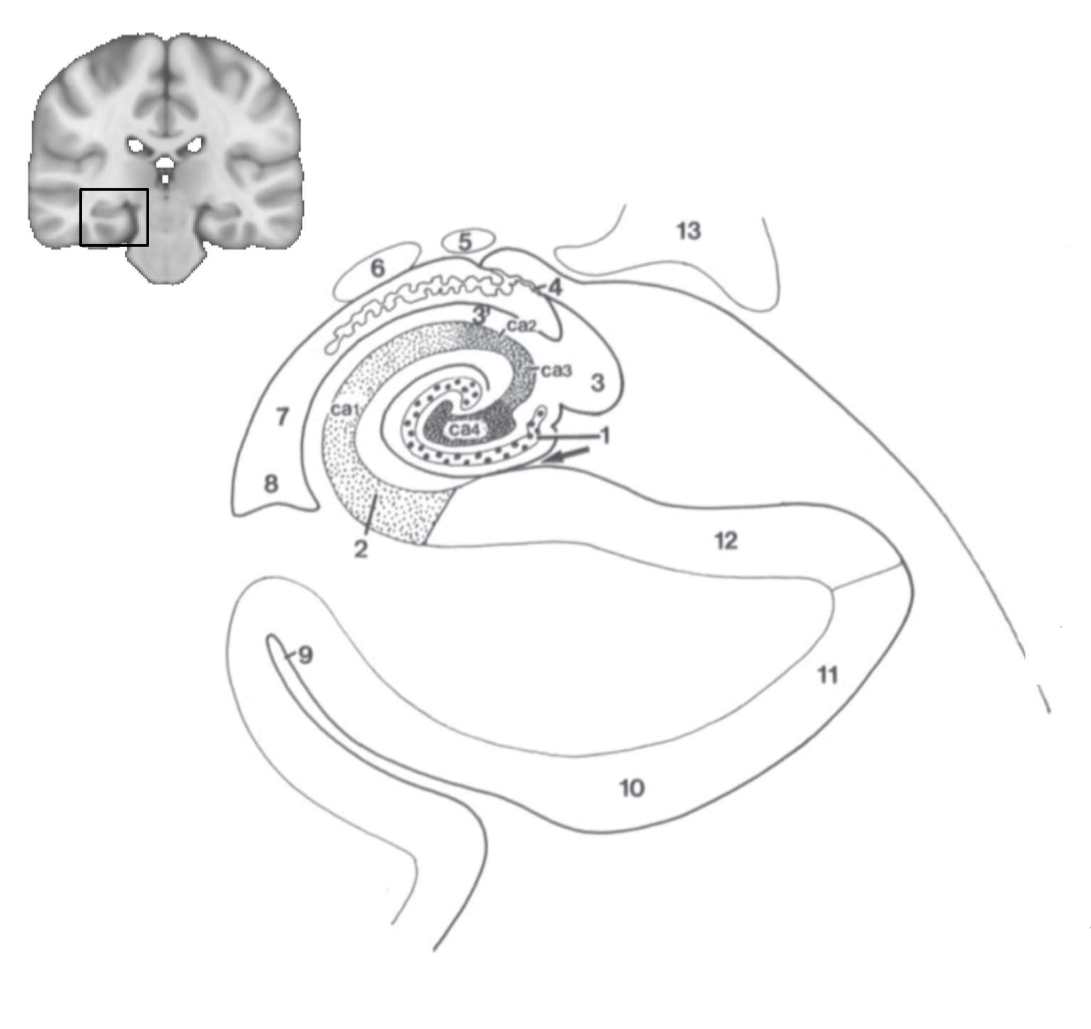

What structure is this?

hippocampus

What is 1?

hippocampus

What is 2?

rhinal sulcus

What is 3?

lateral ventricle

What is 4?

thalamus

What is 5?

entorhinal cortex

What is 6?

perirhinal cortex

What is 7?

parahippocampal cortex

What is 1?

gyrus dentatus

What is 2?

cornu ammonis

What is 3?

fimbria

What is 3’?

alveus

What is the arrow pointing to?

happicampal sulcus

What is ca1, ca2, ca3 and ca4?

fields of cornu ammonis

What is 4?

tela choroidea

What is 5?

stria terminalis

What is 6?

tail of caudate nucleus

What is 7?

temporal horn of lateral ventricle

What is 8?

collateral eminence

What is 9?

collateral sulcus

What is 10?

parahippocampal

What is 11?

entorhinal area

What is 12?

subiculum

What is 13?

lateral geniculate body